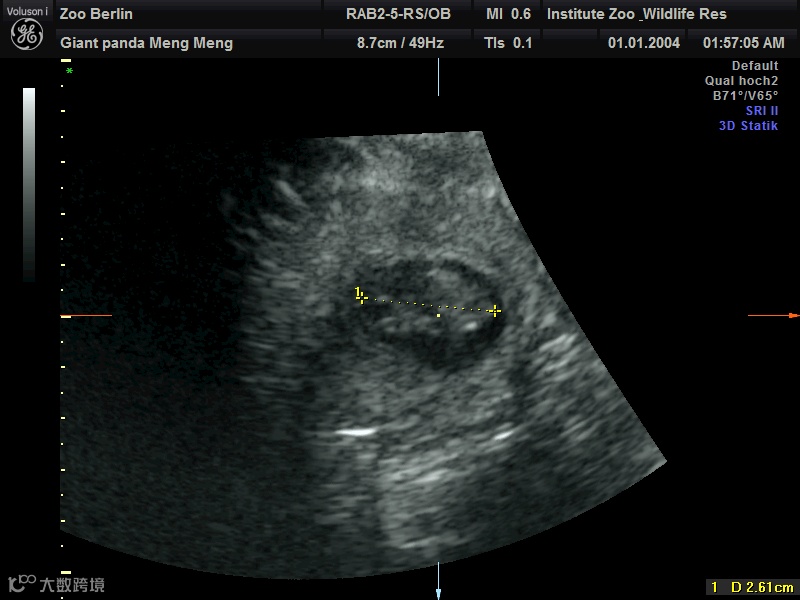

在园方11日上午进行的超声检查中,工作人员清楚地检测到两个熊猫胎儿的心跳。目前两个胎儿身长约2.5厘米。